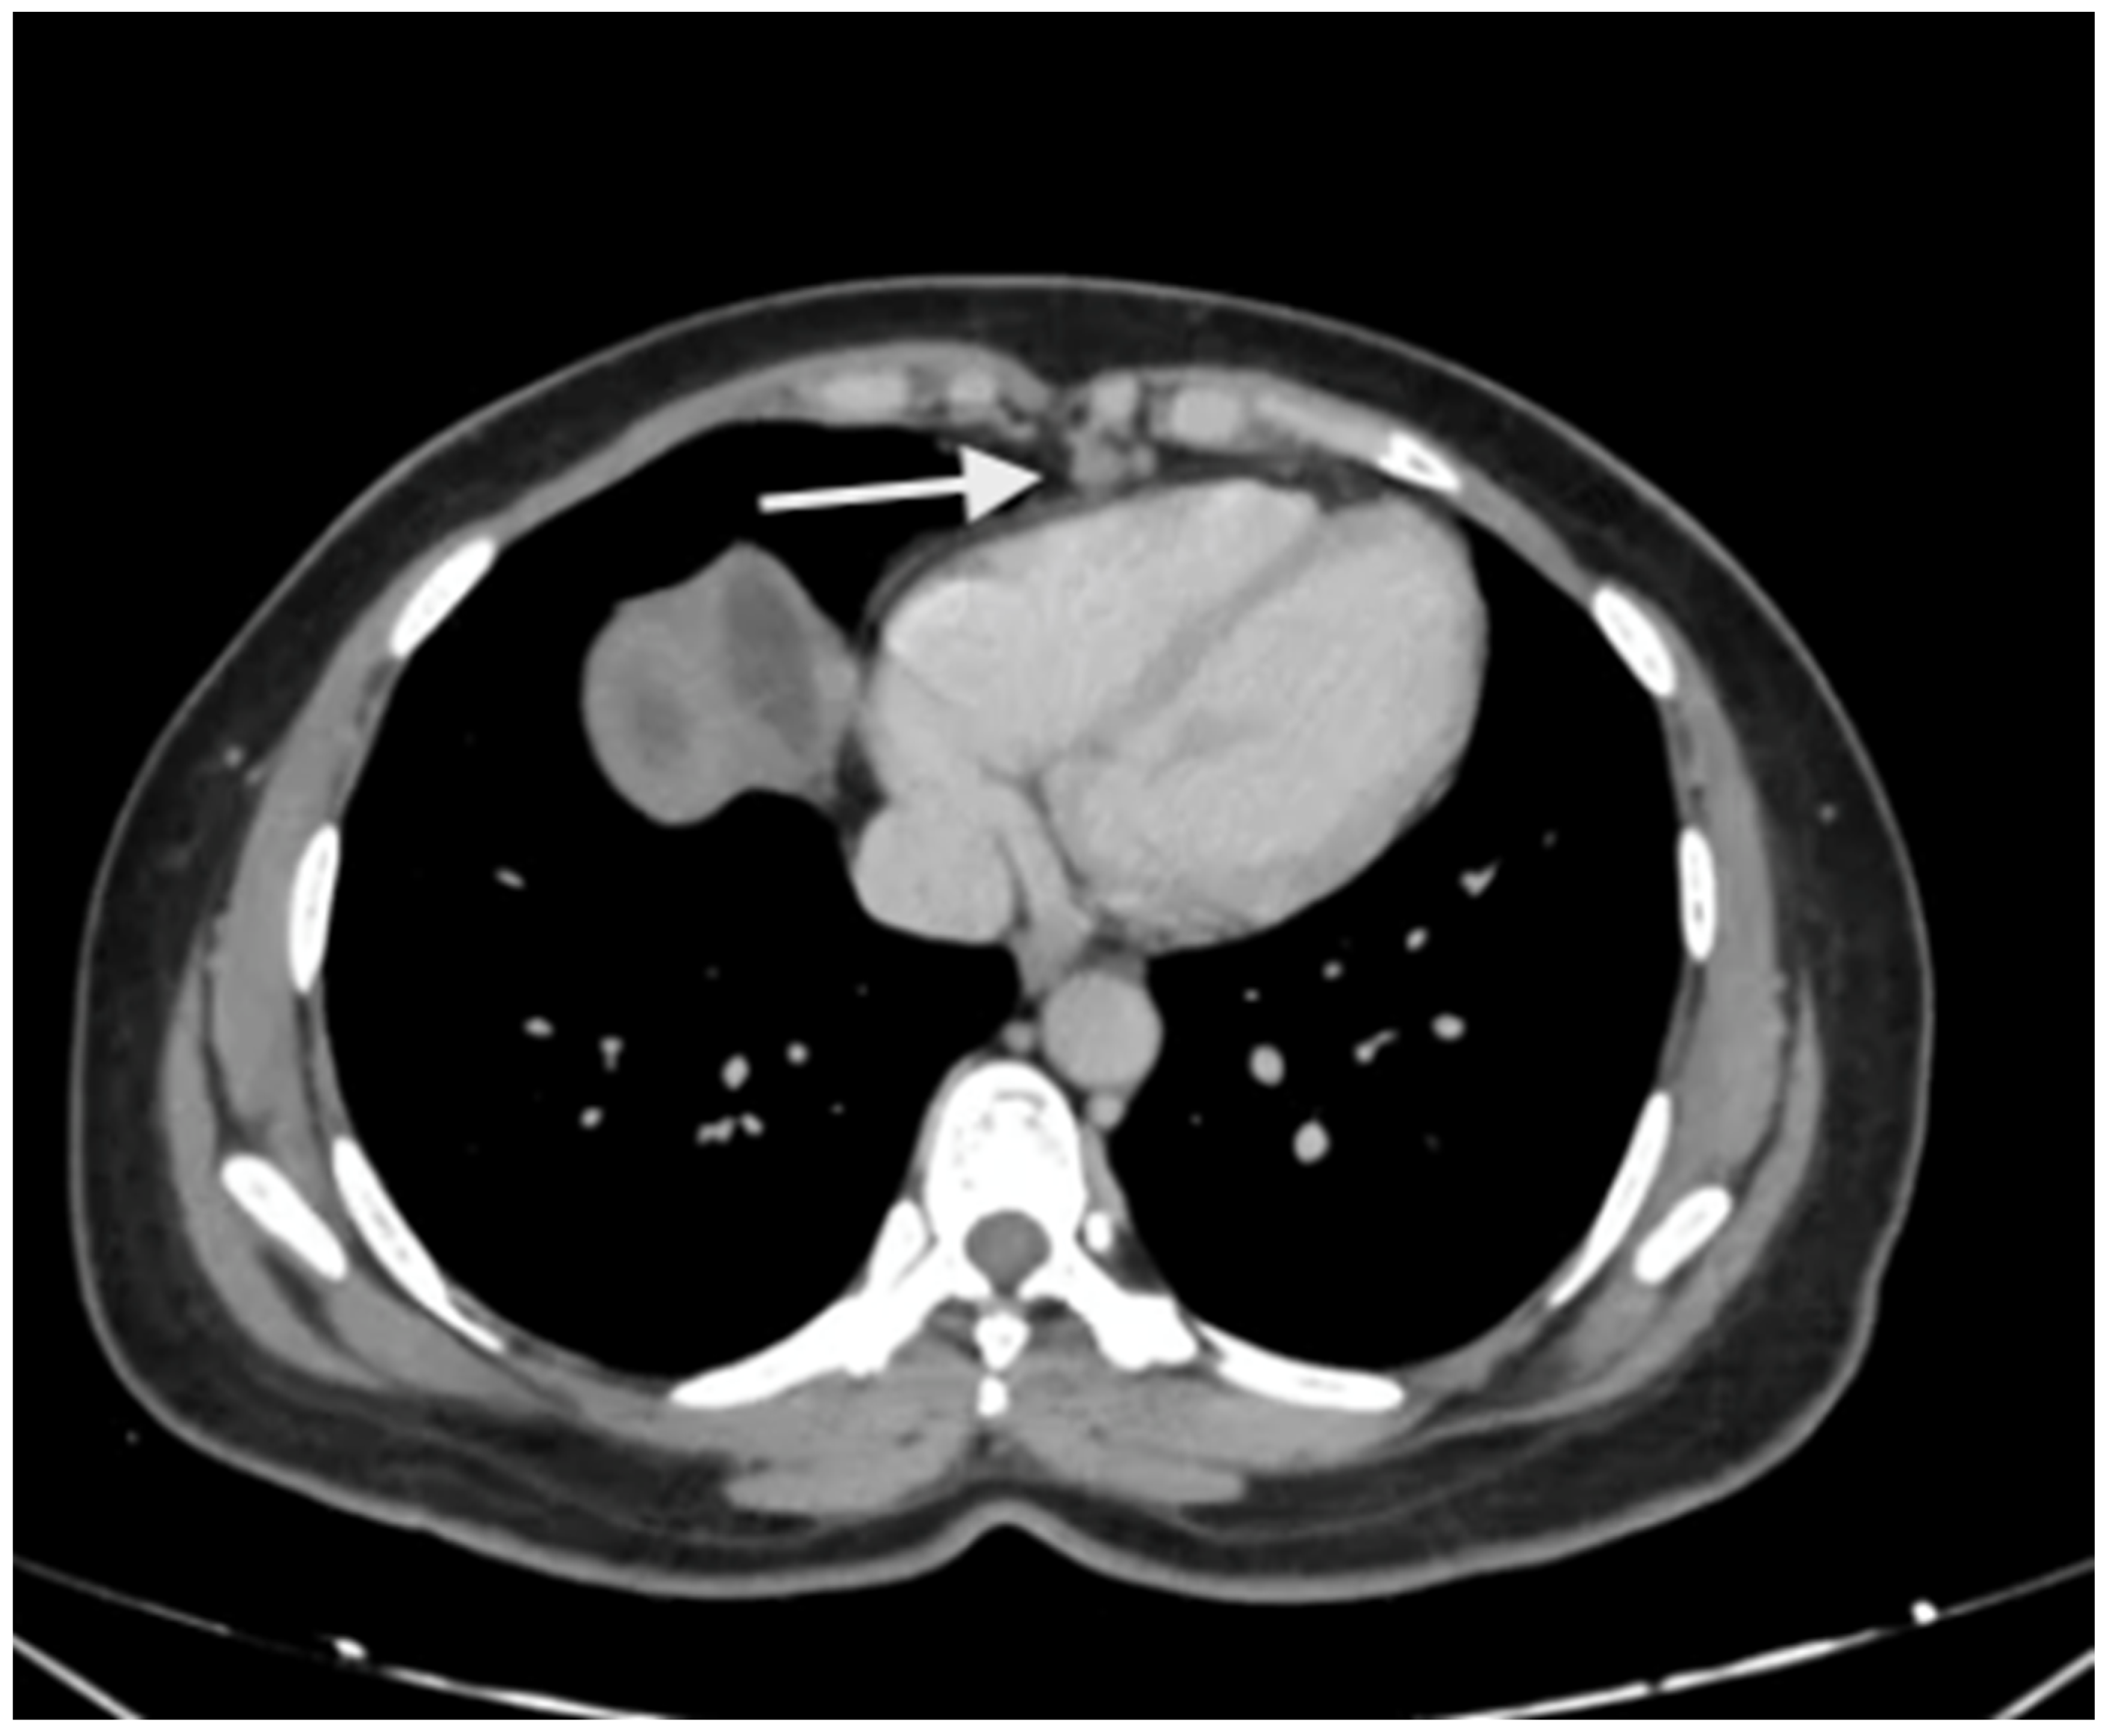

There are no studies evaluating the performance in the upper abdomen, but subtle peritoneal thickening and nodularity are more accurately detected on MRI compared to a CT scan (Figure 3) [53]. The regional lymph node stations described above should be studied on imaging to identify the nodal disease (Figure 4). Considering disease in the upper abdomen alone, extensive disease in the gastrocolic ligament infiltrating the head of the pancreas, extensive infiltration of the stomach, disease infiltrating the porta hepatis, and diffuse and massive involvement of the subphrenic region are pointers of extensive disease that is not amenable to a complete cytoreduction. No one finding can be considered in isolation, and it is the overall disease extent and the general condition of the patient that are considered while deciding to proceed with CRS or not. Though many surgeons perform a staging laparoscopy to select patients for CRS, these obvious signs of inoperability on imaging could avoid an unnecessary surgical procedure [54].

Figure 4.

Enlarged supradiaphragmatic nodes in a patient with advanced epithelial ovarian cancer with upper-abdominal disease. Based on the morphology, they appeared to be metastatic and this was confirmed on pathology after resection of these nodes during CRS.